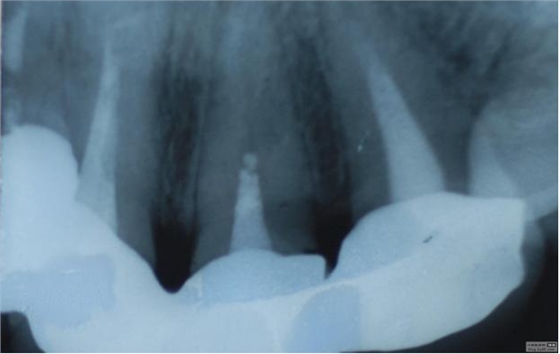

病例1 由于根管充填不完善造成修復(fù)體拆除

修復(fù)后出現(xiàn)根尖周炎癥狀 根管再治療后病變愈合